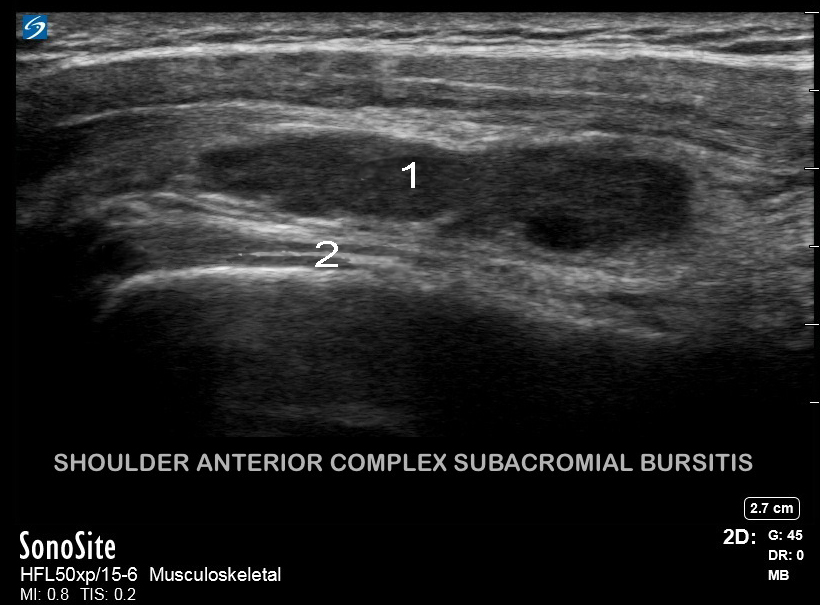

肩部前侧复杂肩峰下滑囊炎

滑囊炎

正常二头肌腱